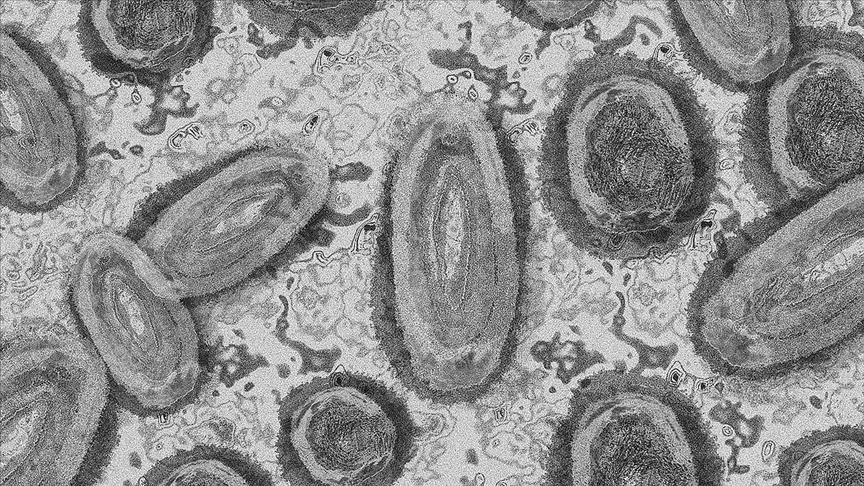

South Korea logs 16 monkeypox cases in 1st week of May

South Korea logged 16 new cases of monkeypox for the first week of May, pushing the country's total to 60, health authorities said Monday.

Monkeypox is transmitted to humans through close contact with an infected person or animal, or with material contaminated with the virus. Patients often start exhibiting symptoms with a fever, enlarged lymph nodes, back pain, and muscle aches before a rash appears on the skin, according to the World Health Organization.